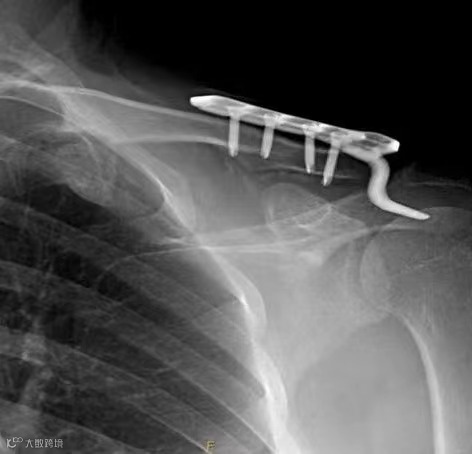

术前

考虑诊断左侧肩锁关节脱位(Tossy III型)

需要进行肩锁关节复位治疗

带袢钢板微创内固定术